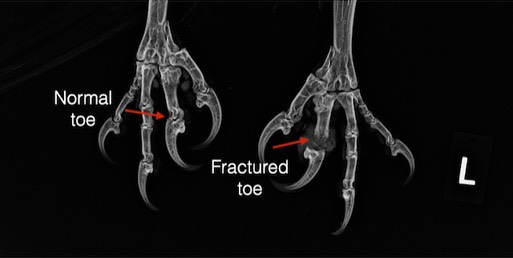

Bald Eagle 22-074

Bald Eagle 22-075